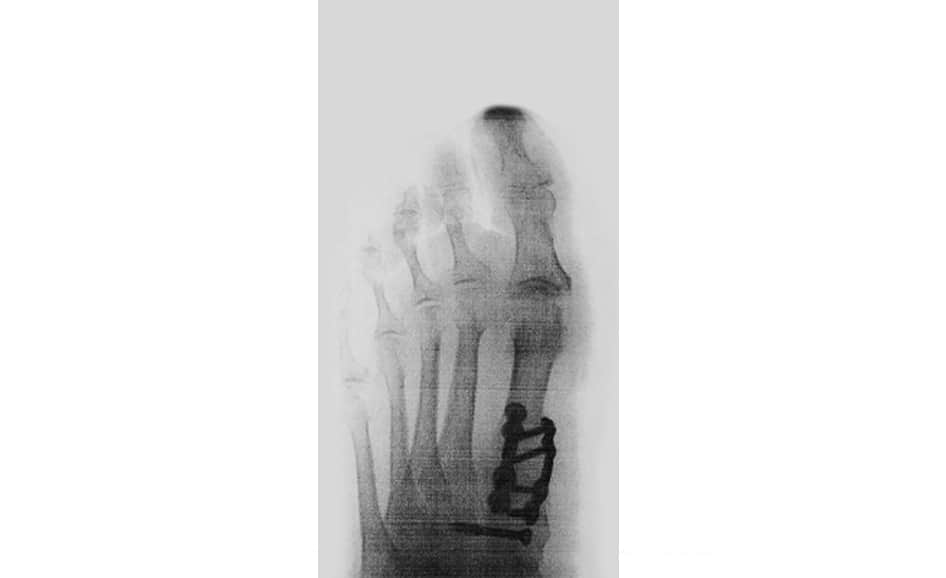

The Lapiplasty 3D bunion surgery is a recently developed type of surgery for the most severe of all bunion deformities. When we address bunion deformities, we must look at the x-rays to determine the severity of the deformity by the alignment, in this case, the malalignment of the first and second metatarsal bone.

The alignment is important to determine because the apex of the deformity is where the correction needs to occur. When the bunion deformity is severe there may be also a problem behind the first metatarsal bone where it connects to the cuneiform bones, many times there is excessive motion at the cuneiform bones this may have to be addressed also at the time of the Lapiplasty procedure.

The Lapiplasty procedure allows for early weight-bearing in a cam walker. Even though this is an advancement over other bunion corrections for severe type a patient must still follow instructions to have an excellent result.

The process that occurs is the patient is seen in the office we take an x-ray and evaluate the patient we then determine the appropriate surgical procedure explaining to them how it is performed. We use digital x-rays to produce a paper copy and draw the procedure on the X-ray and review with a video the Lapiplasty procedure. Review the sedation and outpatient postoperative requirements and instructions for the patient to follow. I review with the patient that I will call them that evening to review any questions or concerns. Follow-up for suture removal is within 2 weeks. The incision is closed with subcuticular closure with steri-strips minimizing any scar formation. It’s important to understand the need for an early range of motion to return to full normal activities. Custom-made Orthotics are sometimes necessary post-surgical to assist the patient.

Lapiplasty is an excellent procedure when indicated for a severe bunion with a flexible foot and hypermobility. Hypermobility is the reason post-surgically Orthotics are sometimes necessary. Sometimes other concurrent problems occur like hammertoes or Tailor’s bunions which can be addressed at the same time for correction.